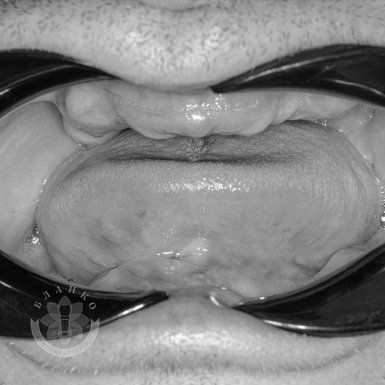

Зубная имплантация — это современное и надежное решение для восстановления утраченных зубов. В стоматологической клинике Бланко мы предлагаем имплантацию зубов «под ключ», что означает полный комплекс услуг — от диагностики до установки коронки, без скрытых платежей и неожиданных расходов.

🔹 Безболезненное лечение – современные методы анестезии обеспечивают комфорт на всех этапах процедуры.